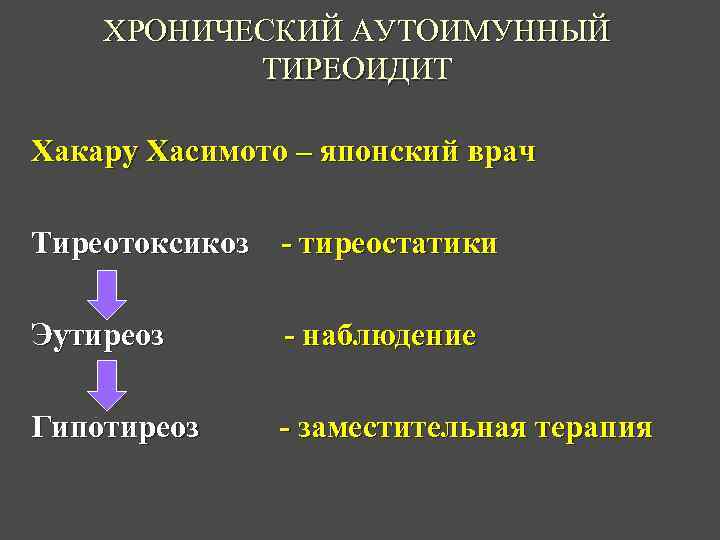

ХРОНИЧЕСКИЙ АУТОИМУННЫЙ ТИРЕОИДИТ Хакару Хасимото – японский врач Тиреотоксикоз - тиреостатики Эутиреоз - наблюдение Гипотиреоз - заместительная терапия